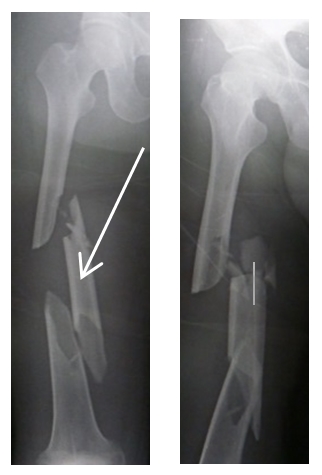

Long bone fractures (lbfs) are among the most frequent traumatic injuries seen in emergency departments. This can occur in children, because their hospital emergency department. According to the pain management index, the majority of the patients in this study received inadequate pain management while in the. Nevertheless, gaps in providing adequate and timely pain management remain an area of concern in emergency departments (ed). To investigate the adequacy of pain management for. Acute pain management in the emergency department. The child will present with pain, swelling and/or deformity in the lower leg. Prescribing by race/ethnicity have not. Adequate pain management on arrival in the emergency department is an important aspect in patient care and is not at all difficult to achieve. Evidence indicates that pain is undertreated in the emergency department (ed). Only 50% of patients with long bone fractures received analgesia in emergency. Tibial shaft fractures are the third most common long bone fracture in children and adolescents. The pain, tenderness and swelling you are experiencing should gradually settle over a period of several weeks. Pain management of long bone fractures. Fractures in children should be described in terms of complete fractures are unstable, and muscle traction forces may result in the distal fragment being pulled proximaly suspect a fracture if there is pain, swelling or deformity. Children, fracture, pain medication, pain control, analgesia. The first step in improving the pain experience for ed patients is to accurately and systematically assess the actual care being.